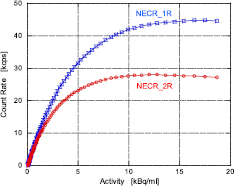

Figure 7 shows the total count rate capability of the system for true, random, and scatter coincidence events, including single events, as a function of the line source activity divided by the total volume of the cylindrical phantom. These data were corrected by subtracting the 176Lu background count rate of 415 cps and 381 cps for the prompt (T + S) and random coincidence rate, respectively, whereas the single background count rate was 520 kcps. The true count rate reached 249 kcps, and seemed to continue to increase. The single count rate also increased over 25 Mcps, suggesting that the dead-time losses were slight. This indicates that the single-event data acquisition system worked well even in the high-count rate regions. The NECR_1R and 2R are shown in figure 8. The peaks of NECR_1R and 2R were 44.7 kcps at 17.5 kBq ml−1 and 27.9 kcps at 11.9 kBq ml−1, whereas SF was 48.3% and 47.2%, respectively.

Standard image High-resolution imageFigure 8. Noise equivalent count rate (NECR) as a function of the line source activity divided by the total volume of the 70 cm cylindrical phantom.

Download figure:

We implemented a single-event data acquisition method with on-the-fly coincidence detection by software built into this PET scanner. The advantage of single-data acquisition for PET is that it allows the ability to use full information of physical parameters for image reconstruction. The timing information of each single event provides us with the optimum timing window and the possibility to adjust for timing delays of each detector, using software. The energy information can be applied for scatter correction, although it was not used in the present study, and may not be used as long as only list-mode data acquisition is implemented. Additionally, there is considerable flexibility in arranging the ring structure, because there is no need to develop coincidence detection circuit boards adopting the ring structure. The count rate capability in the system was evaluated using a 70 cm long cylindrical phantom according to NEMA NU 2-2012. The maximum count rate exceeded 25 Mcps and 2.3 Mcps for single events and coincidence events (prompt and random), respectively, and can potentially reach even higher values. The dead-time losses in singles would be primarily caused if the 5:1 multiplexer selected one unit among the units irradiated γ-rays in the detector layer board, although this could be fairly suppressed by using independent readout detectors. Apart from that, the maximum count rate would be limited by the data acquisition transfer speed if the singles would not be saturated by the dead-time losses, and approximately 120 Mcps was estimated to be the maximum single count rate, assuming that the count rate was uniform for each detector module. The on-the-fly coincidence detection by software operated successfully, without any data loss, sufficiently so for clinical brain studies using 11C-MeQAA injection, because the maximum single count rates in the studies were less than 25 Mcps. However, attempts should be made to assess this by 15O water studies, which typically use very high injection activities. The real-time coincidence detection engine was created by common server computers using software. If the single count rate is considerably increased, coincidence detection may not follow. The computer power; however, has increased exponentially annually; thus, software coincidence detection is likely to become routine. The peak NECR_2R was 27.9 kcps at 11.9 kBq ml−1. This value is lower than that of high resolution research tomograph (HRRT) and jPET-D4 brain PET scanners, mainly due to the 3/4 shorter axial FOV.